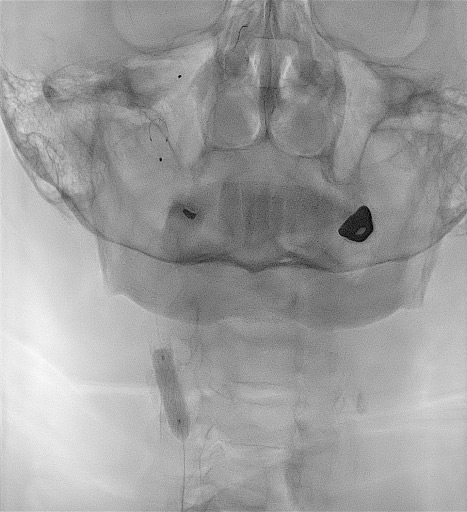

Supra-aortic trunks angiography

Type 1 aortic arch

Slow left hemisphere circulation with contralateral and posterior compensation

Functional occlusion of LICA partially compensated through slow antegrade flow and LECA flow

Right carotid axis

Severe bulb calcification, severe calcified stenosis of the RICA, and pseudo-occlusion of RECA. Severe tortuosity of right internal carotid distally to stenosis